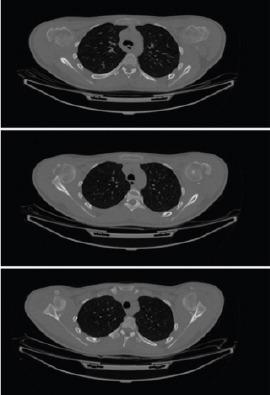

A 16-year-old boy presented to the emergency department with reduced range of movements in both shoulders. Six weeks prior he had suffered an epileptic seizure. X-rays confirmed bilateral anterior shoulder dislocations with displaced greater tuberosity (GT) fractures. Staged open reduction was performed in the right and then left shoulder. Coracoid osteotomy with takedown of the malunited GT fracture was needed to assist with gradual soft tissue contracture release and a successful relocation. Latarjet procedure was then performed and the GTs were fixed using rotator cuff anchors. At 6 months post-operation, on the right side, he achieved forward flexion to 150o and abduction to 120o. On the left side, forward flexion was 110o and abduction was 90o. X rays showed satisfactory maintenance of the reduction without signs of avascular necrosis of the humeral head.

一名16岁男孩因双肩活动范围受限就诊于急诊科。六周前他曾癫痫发作。X线证实双侧肩关节前脱位伴大结节(GT)骨折移位。先对右侧肩关节进行分期切开复位,随后是左侧。需要进行喙突截骨并切除愈合不良的大结节骨折以辅助逐渐松解软组织挛缩并成功复位。然后进行Latarjet手术,使用肩袖锚钉固定大结节。术后6个月,右侧肩关节前屈达150°,外展达120°。左侧肩关节前屈为110°,外展为90°。X线显示复位维持良好,无肱骨头缺血性坏死迹象。